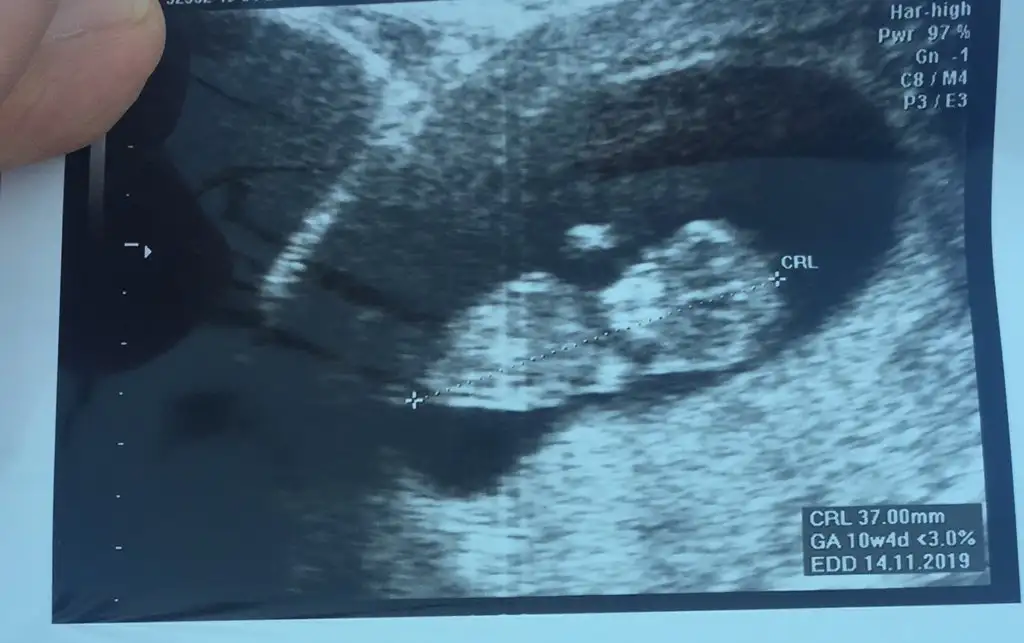

Fotosu yok mu kuzunun? Gün olarak paralel olabiliriz seninle kendi bebisimi görmüş gibi olurum valla 😍

Eklentiler

• C01A609C-470F-4702-AA19-13C9406E7DA1.webp

C01A609C-470F-4702-AA19-13C9406E7DA1.webp

27,3 KB · Görüntüleme: 58

• D8130AD8-8DAF-4C73-980A-7B2C7B525709.webp

D8130AD8-8DAF-4C73-980A-7B2C7B525709.webp

33,5 KB · Görüntüleme: 63